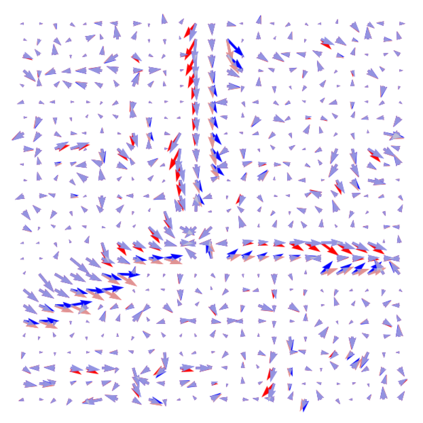

Vessel segmentation is an essential task in many clinical applications. Although supervised methods have achieved state-of-art performance, acquiring expert annotation is laborious and mostly limited for two-dimensional datasets with a small sample size. On the contrary, unsupervised methods rely on handcrafted features to detect tube-like structures such as vessels. However, those methods require complex pipelines involving several hyper-parameters and design choices rendering the procedure sensitive, dataset-specific, and not generalizable. We propose a self-supervised method with a limited number of hyper-parameters that is generalizable across modalities. Our method uses tube-like structure properties, such as connectivity, profile consistency, and bifurcation, to introduce inductive bias into a learning algorithm. To model those properties, we generate a vector field that we refer to as a flow. Our experiments on various public datasets in 2D and 3D show that our method performs better than unsupervised methods while learning useful transferable features from unlabeled data. Unlike generic self-supervised methods, the learned features learn vessel-relevant features that are transferable for supervised approaches, which is essential when the number of annotated data is limited.